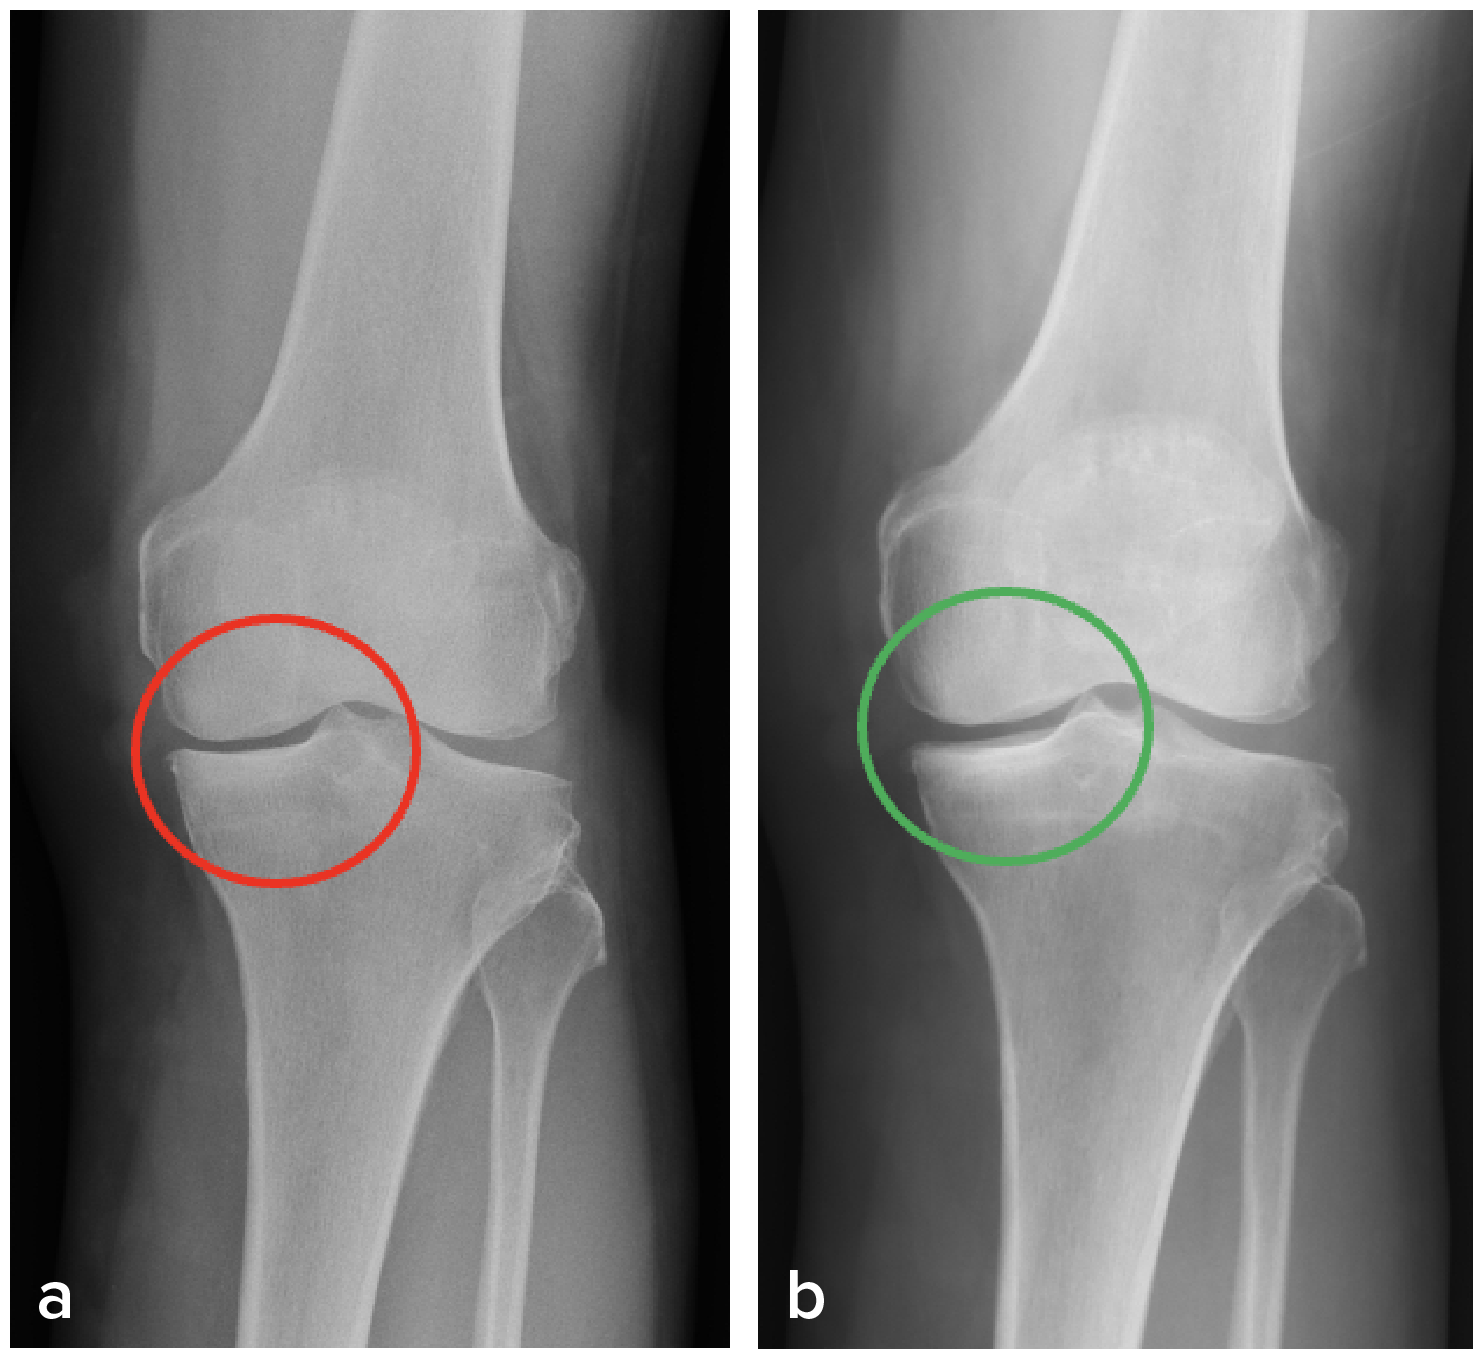

If implemented in time, knee OA is not only preventable but also curable by SKC. SKC stops knee cartilage damage and facilitates its regeneration. Contrary to the common notion in mainstream medicine that worn cartilage cannot grow back, we have seen in our patient’s countless real-life re-growth of their worn-out cartilage just by SKC. Take a patient for example (Fig. 2):

the radiographic manifestation could be observed in both his knees (b).